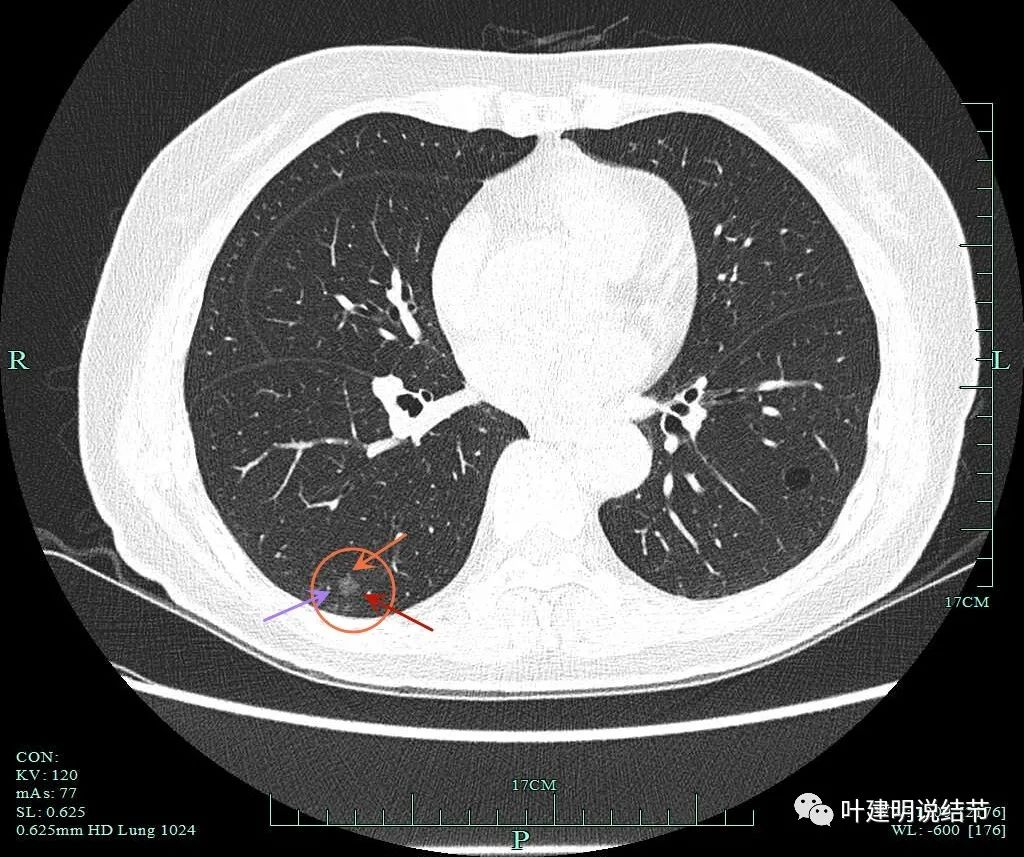

病灶6:右上叶后段混合磨玻璃结节,实性成分少,总体密度不高,但轮廓清,有血管进入。单凭密度应该原位癌或不典型增生,但因血管征存在升一级考虑,微浸润性腺癌不能除外。有一定风险性,可考虑干预切除或4-6个月复查随访。

病灶8:右下叶磨玻璃结节了,轮廓清,血管贴边,边缘显毛糙。

有明显小血管进入,小血管有异常增粗。从密度考虑不典型增生可能性大,但因血管进入升一级考虑,原位癌可能性大点。如果没有上叶病灶6存在,此灶可随访,近期风险不算高。

病灶6重建后显示血管进入与穿行。

病灶8重建后显示血管与结节间没有间隙,而且瘤肺边界很清。